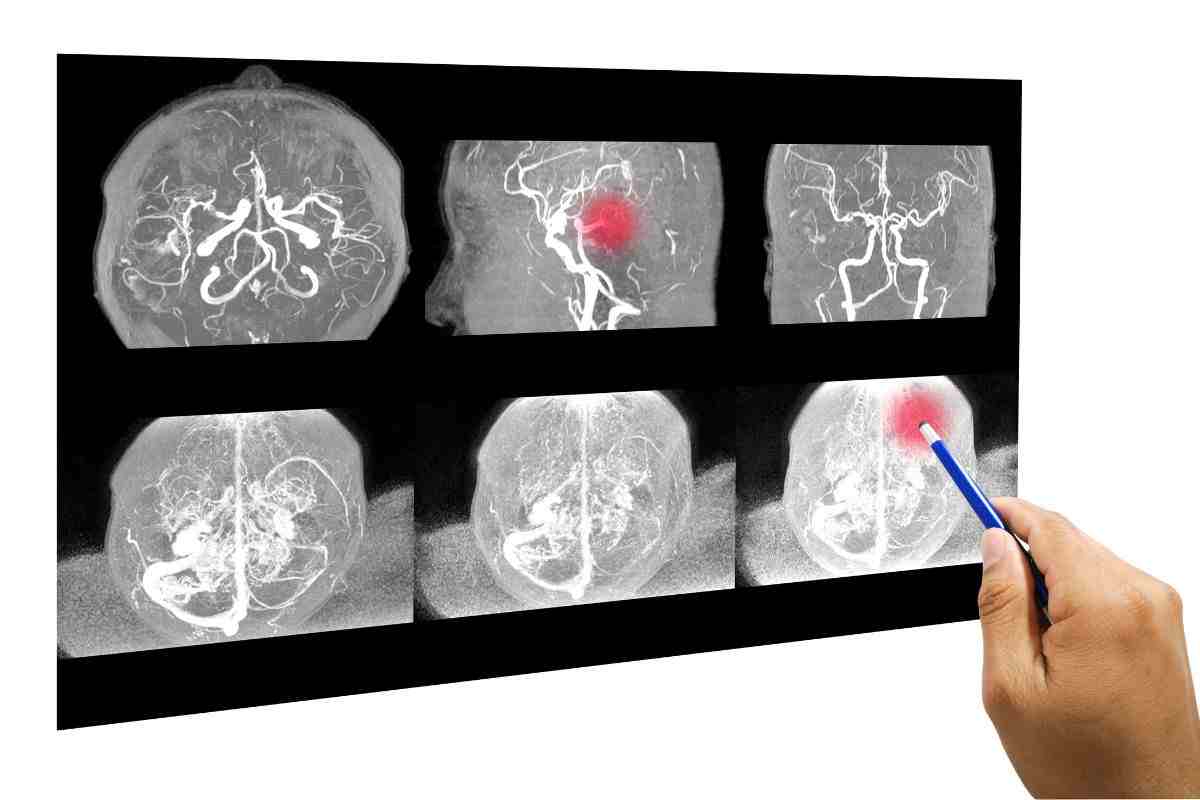

L’ischemia cerebrale è una patologia di natura circolatoria che interessa il cervello e si manifesta con la comparsa improvvisa di un deficit neurologico dovuto all’interruzione dell’afflusso sanguigno in una parte del cervello. Questa interruzione può essere causata dall’occlusione di un’arteria (ictus ischemico) o dalla rottura di un vaso sanguigno (ictus emorragico).

Al contrario, l’ictus emorragico, meno frequente ma più grave, è spesso causato da valori elevati di pressione arteriosa o dalla rottura di malformazioni congenite come l’aneurisma. In questi casi, il sanguinamento può localizzarsi negli spazi esterni al cervello, provocandone danni indiretti.